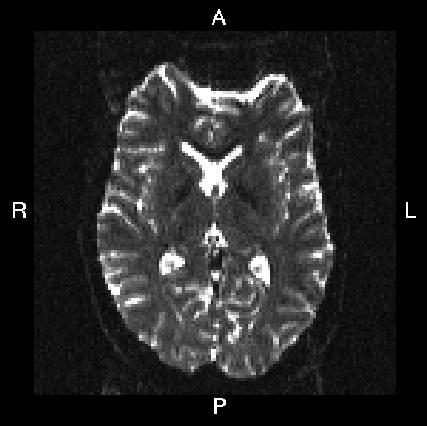

Here is a visual "cheat sheet" for what to put into your --acqp file

| What you see in FSLeyes |

![]() |

|---|---|---|---|---|

| First three columns in --acqp file | 0 1 0 | 0 -1 0 | 1 0 0 | -1 0 0 |